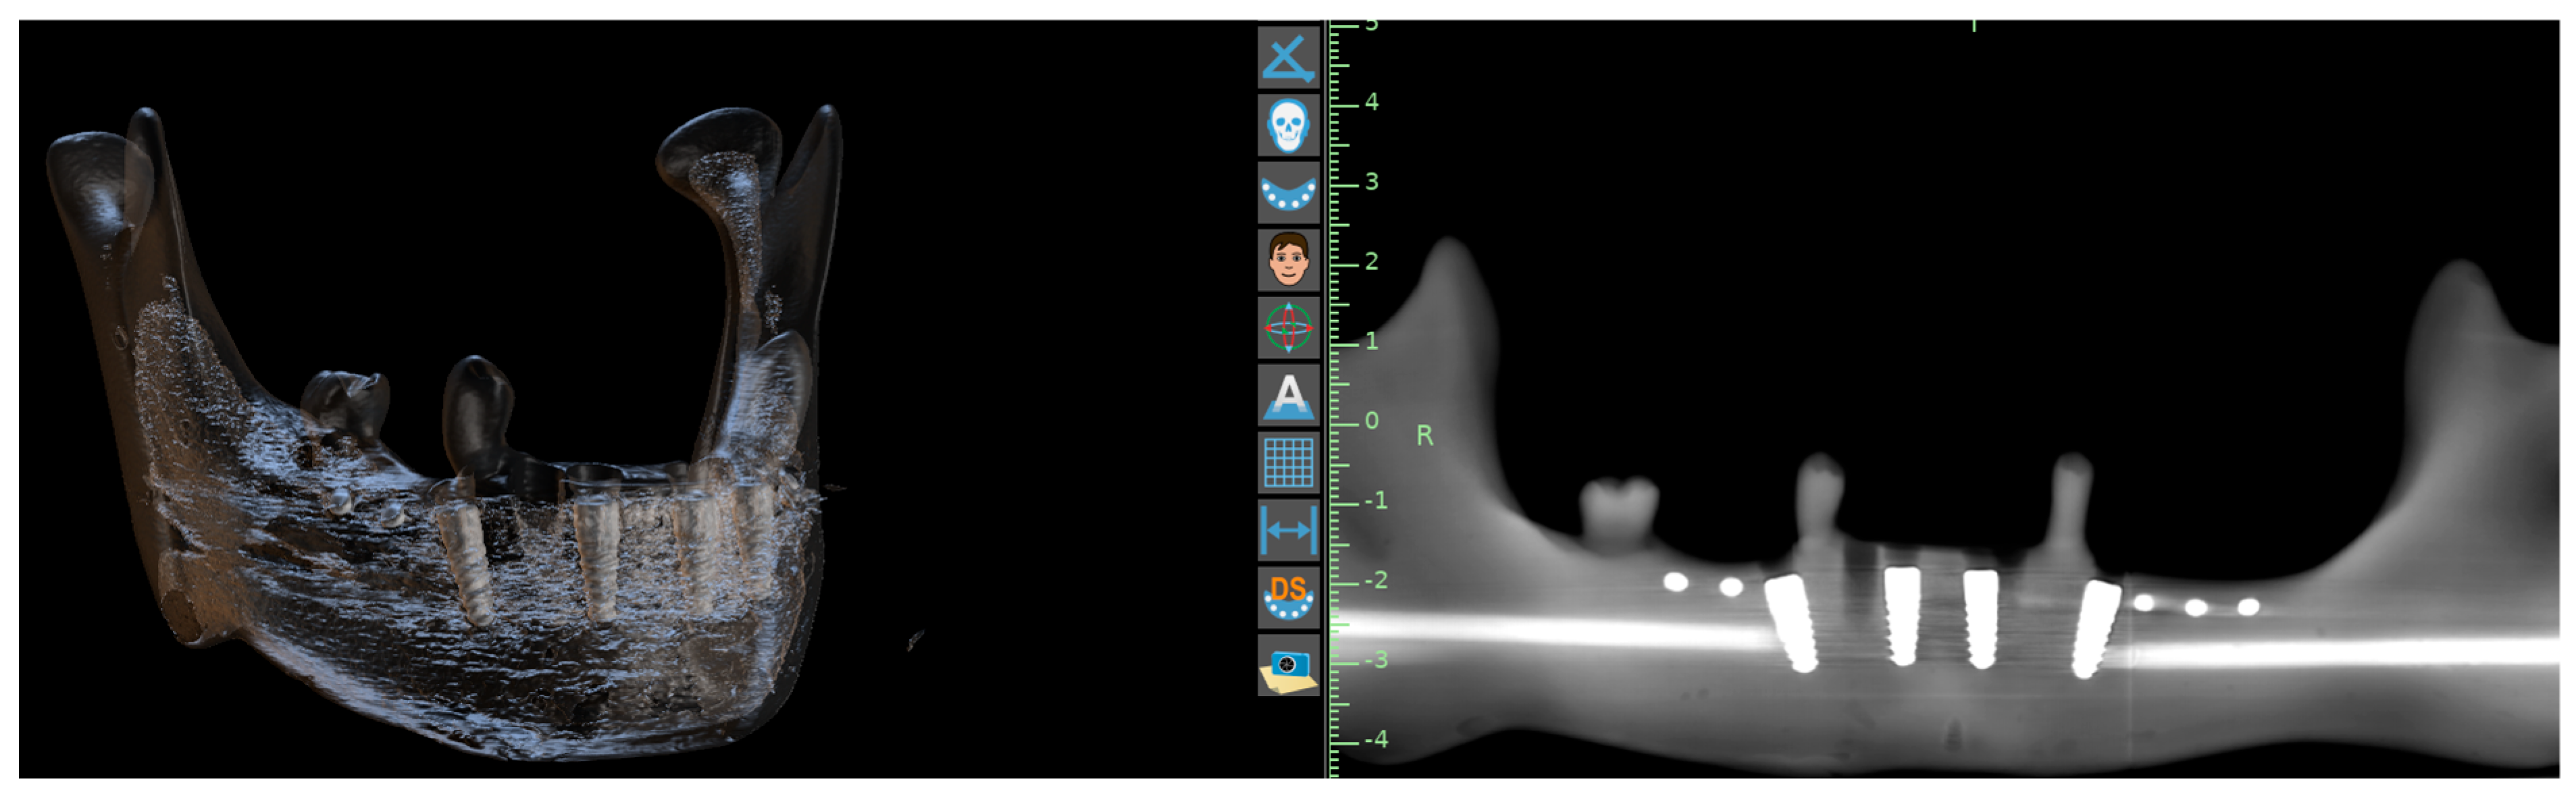

2. Material and Methods